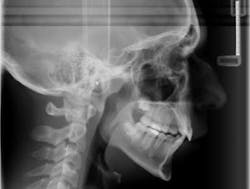

Skeletal Class II problems are due to mandibular deficiency or downward-backward rotation of the mandible caused by excessive vertical growth of the maxilla. (1) When a skeletal Class II patient presents with the request to have his or her teeth aligned, the following factors must be considered:

Case report A healthy 16-year-old male presents with Class II bite, an obtuse nasolabial angle, a slight, long concave profile with deficiency in the growth of the mandible, and inadequate spacing for the maxillary teeth. What are the options and talking points for this treatment plan?1. There is likely very little growth potential left in this patient, so trying to capture any remaining growth would be minimal.

3. In reference to point No. 2, orthodontic treatment planned without mandibular jaw advancement surgery in these types of cases generally will build in more dental compensations for skeletal variation (2), as the profile is compromised even more with a wider nasolabial angle, longer profile, and thus limiting the ability for any future facial profile correction.

4. The ideal treatment and recommendation would be to perform a lower jaw advancement surgery to give an ideal position of skeletal and dental components. Worms et al. reported that the total interrelationships of surgical and orthodontic contributions are in the best care and interest of the patient long term. (2)

It could be concluded with the aforementioned talking points that there is not a right or wrong way to proceed in cases like this. Some options are better than others, but this is the take-home point: If a Class II patient (as presented herein) does have the upper 4’s removed, it exacerbates the existing profile and limits virtually any potential for a correction of profile in the future. It is, therefore, vital to discuss all risks, benefits, complications, and alternatives so the patient can make the best decision possible. Assuming no regard to cost or possible complications, the mandibular advancement would be considered by most to be the preferential treatment in this case, as it resolves the core problem — mandibular deficiency. In this case, the patient was not willing to undergo a surgical procedure at this time, so the treating orthodontist advised the family against the removal of maxillary teeth in order to preserve facial profile and allow for possible future mandibular advancement procedure.